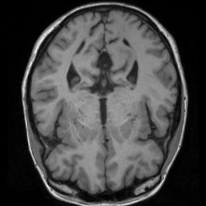

4.4 Qualitative Evaluation

In Figure 5 we analyze the prediction quality of our and compared approaches in a qualitative way. Considering modality propagation in MRI, we see that usage of uncertainty-aware patch invariance (UAPI) gives a better detailed weighting of the cerebrospinal fluid in the middle of the brain. In general, employing patch invariance yields better preservation of fine structures. This observation also applies to accelerated MRI enhancement. In particular, CUT and UAPI provide comparatively sharper knee images with more high-frequency details than the other methods.